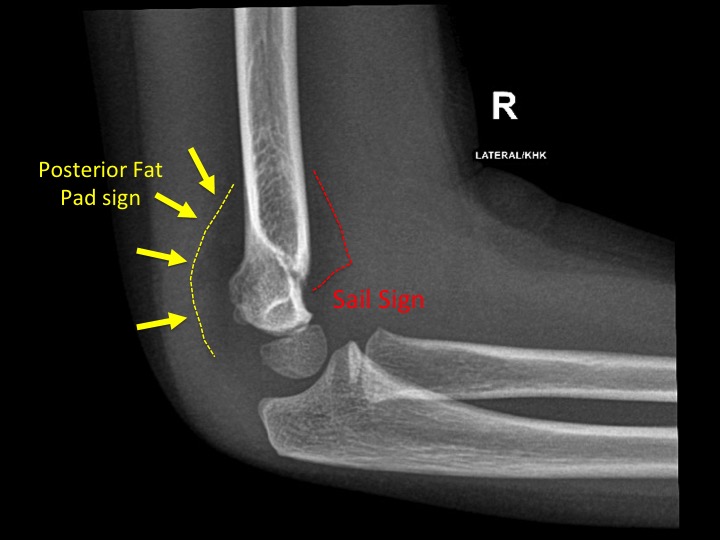

Fat pad sign (signo de la almohadilla grasa)

¿Qué indica el signo de la almohadilla grasa en Rx lateral de codo? (teórico clínico | poca relevancia)

La grasa periarticular normalmente está pegada al hueso (anterior: invisible o apenas visible; posterior: invisible)

Derrame articular → grasa se desplaza/levanta → visible como triángulo radiolúcido

Fat pad anterior elevada: inespecífica pero sugiere derrame

Fat pad posterior visible: SIEMPRE patológica → derrame → sospechar fractura oculta (especialmente cabeza del radio)

En niños con Rx "normal" pero fat pad positivo → tratar como fractura hasta probar lo contrario